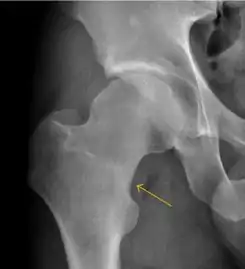

There are other pathological conditions that can affect the hip joint and radiographs help to make the appropriate diagnosis. Acute bacterial septic arthritis can be diagnosed by radiographs when a fast regional osteoporosis and destructive monoarticular process develops (Figure 1(f)). In case of tuberculous or brucella arthritis it is manifested as a slow progressive process, and diagnosis may be delayed.[1]

Synovial chondromatosis can be confidently diagnosed by X-ray when calcified cartilaginous chondromas are seen. However, other synovial proliferative processes, such as pigmented villonodular synovitis, require MRI for accurate diagnosis, although noncalcified synovitis can be suspected in radiographs by indirect signs, such as soft tissue swelling and/or erosions in the femoral head, femoral neck, or acetabulum (Figure 7).[1]